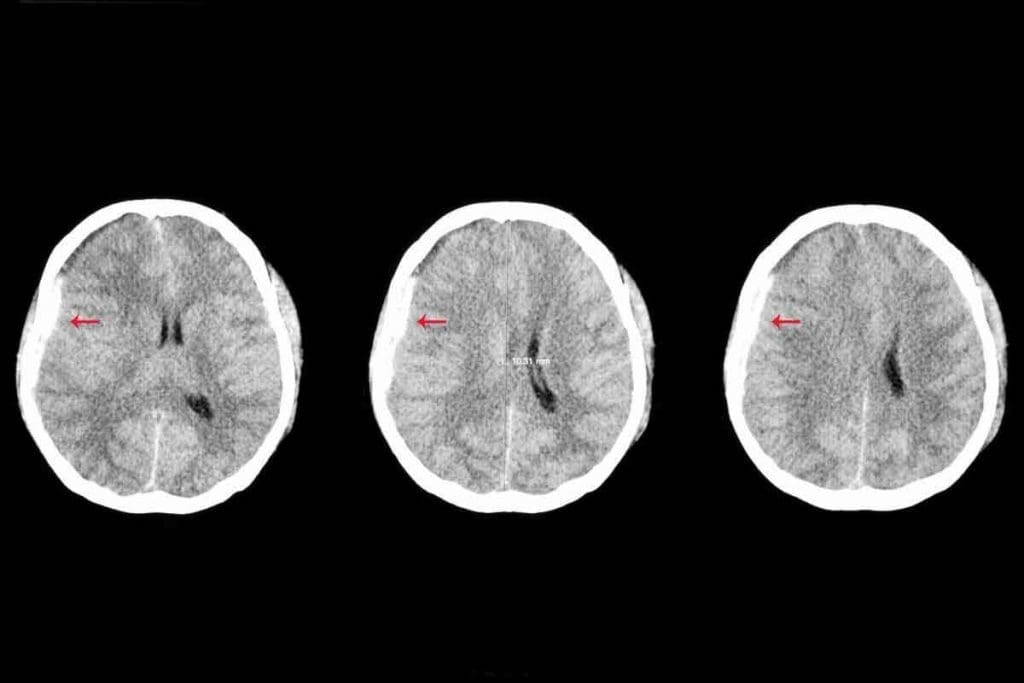

Brain Tumor CT Scan: What Doctors Look For

On a CT scan, tumors show up as masses with odd shapes. They might look hypodense (darker) or hyperdense (lighter) than the brain. Their edges are often irregular.

Doctors check the tumor’s size, where it is, and if it’s pushing on brain structures. They also look for signs like calcifications or bleeding inside the tumor.